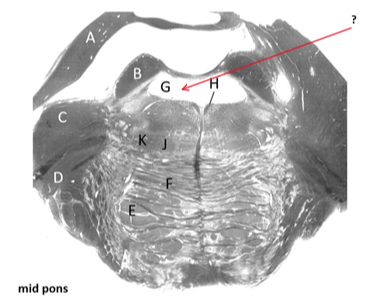

Name this and state its function.

State all components it controls.

Medial longitudinal fasciculus.